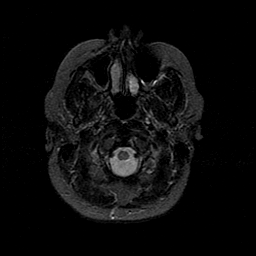

MR Study #1 -- Slice #6